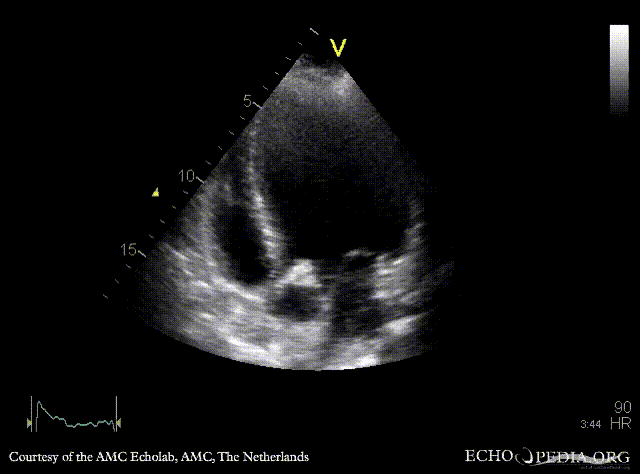

A4CH: dilated left ventricle A5CH: vegetations on aortic valve, dilated left ventricle